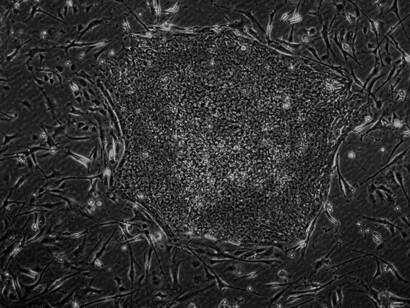

Mesenchymal stem cells (MSCs) are stromal cells that can differentiate into many lineages and self-renew. Numerous tissues, including the umbilical cord, endometrial polyps, menstrual blood, bone marrow, adipose tissue, etc., can yield MSCs.

Cells from bone marrow or adipose tissue are harvested, processed, and then reintroduced into the injured area. This strategy allows your body to repair naturally, resulting in less pain and a speedier recovery.